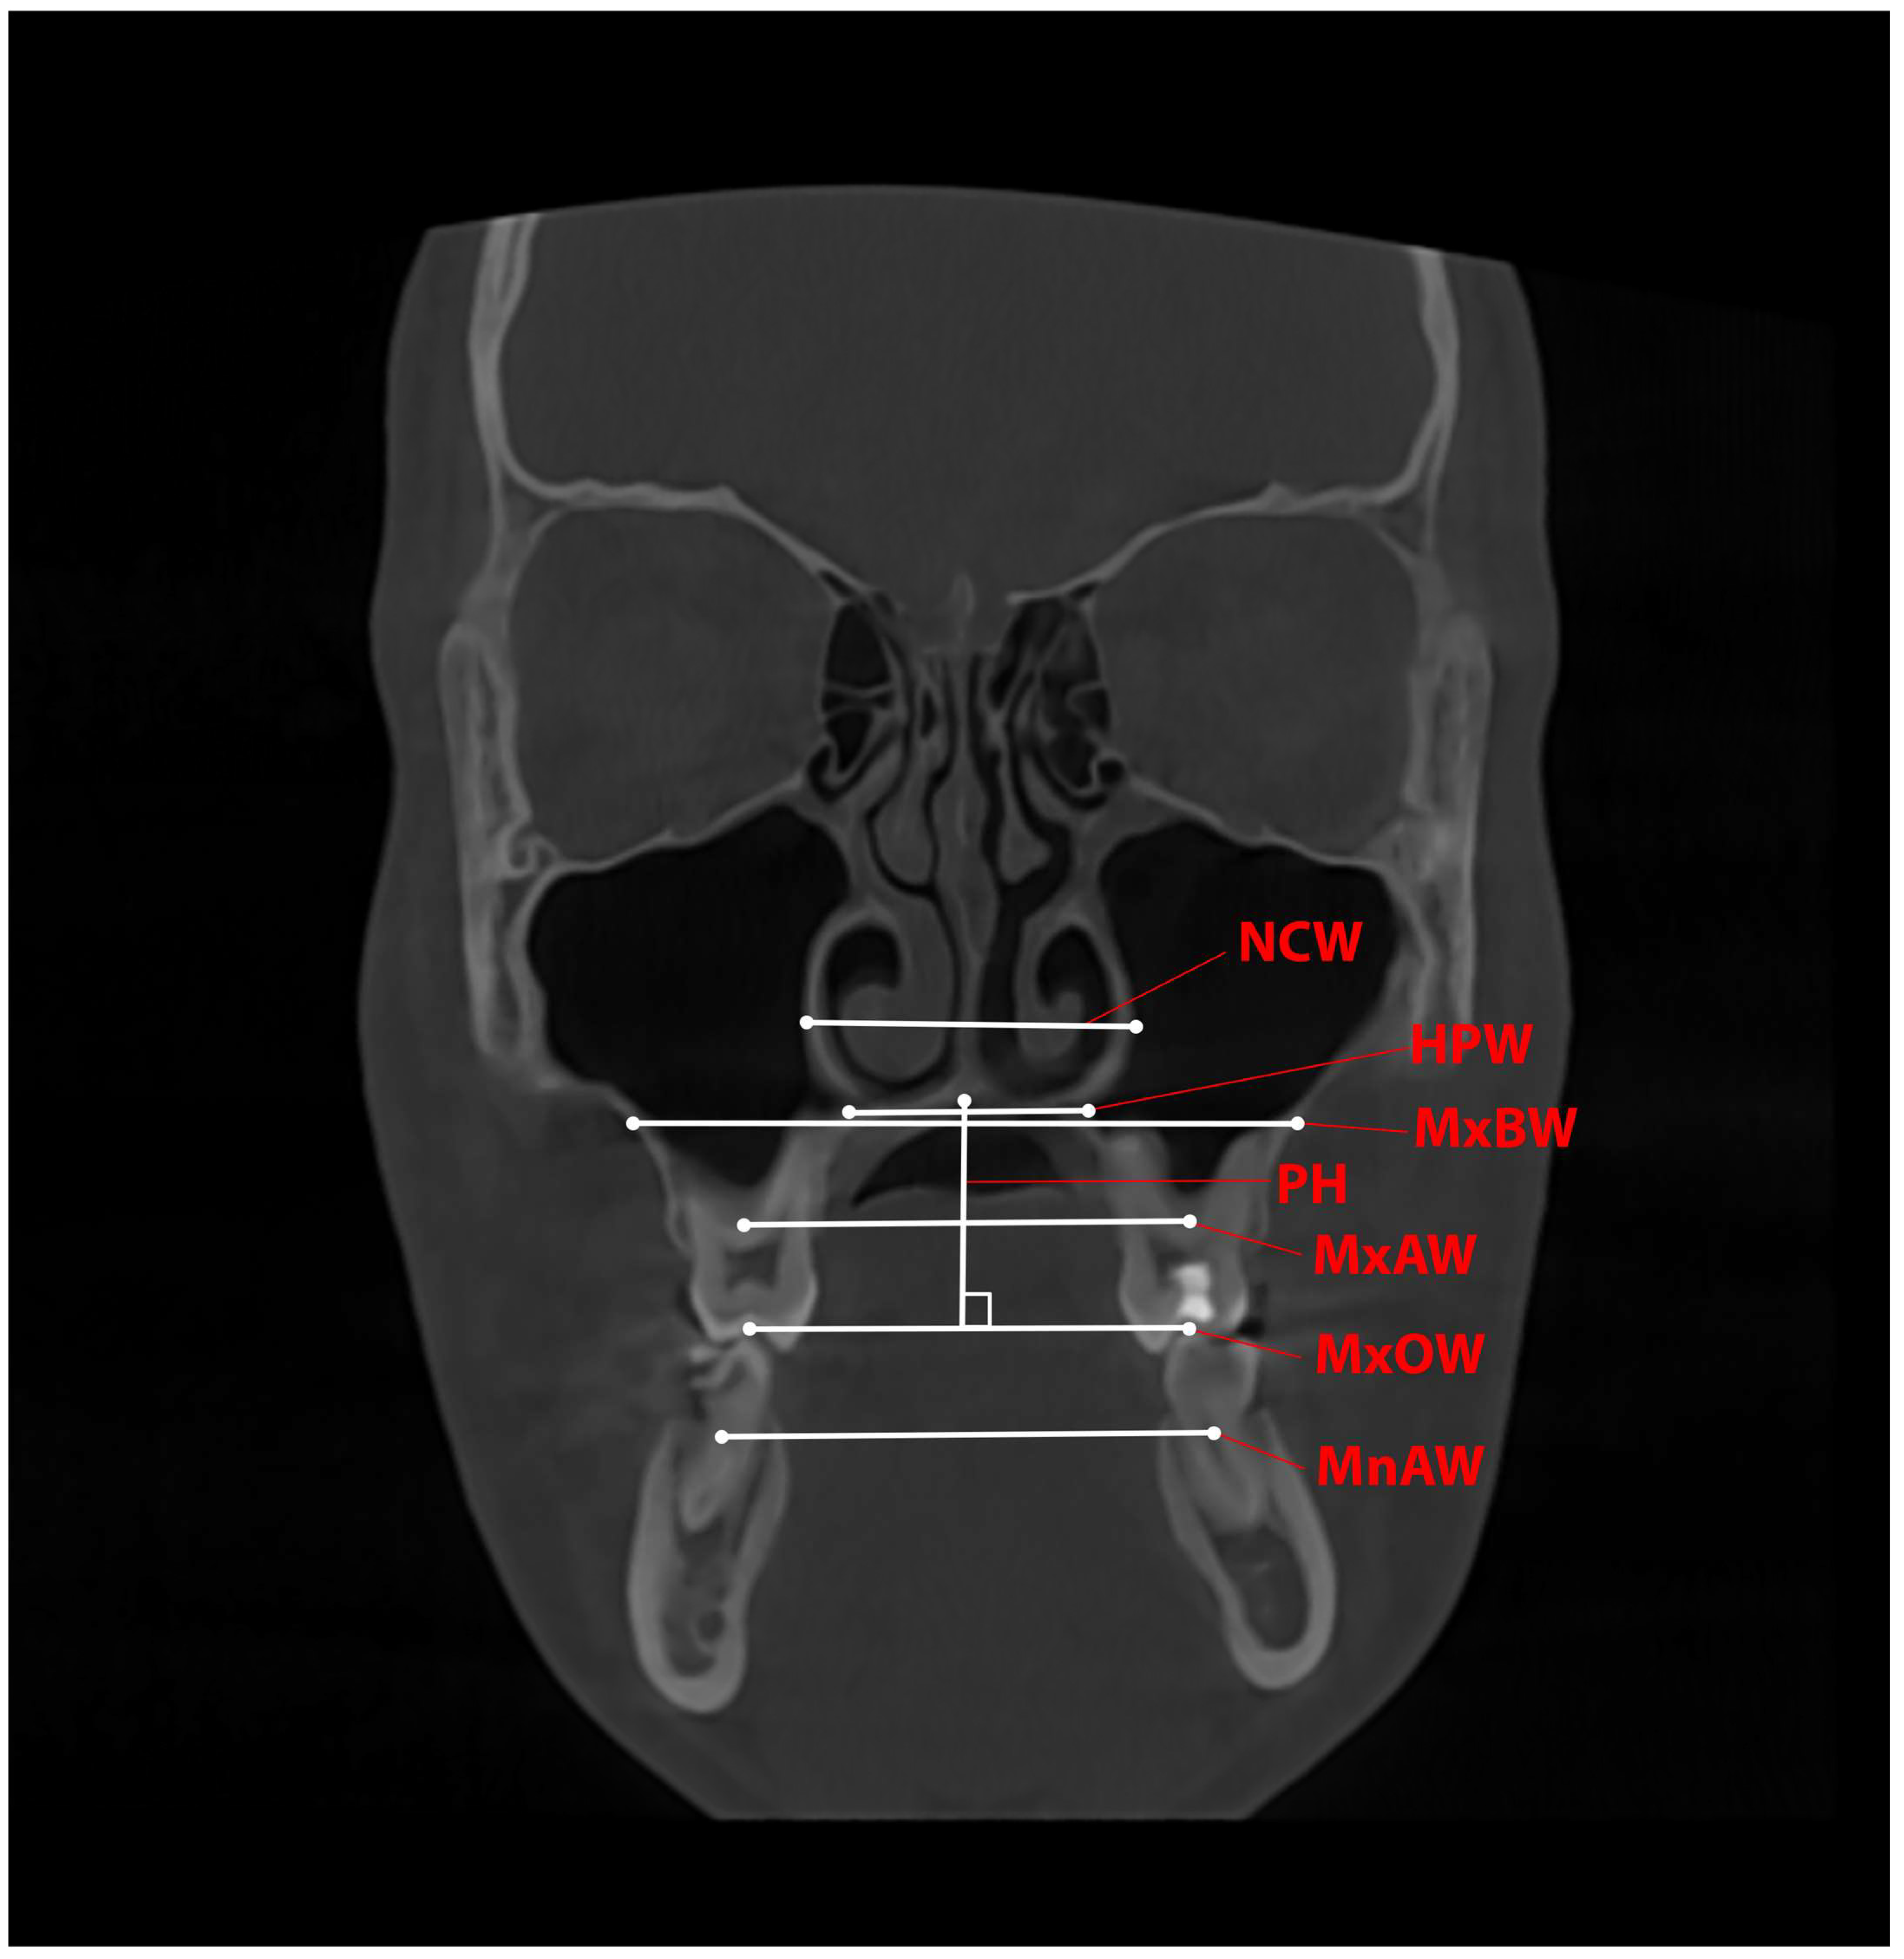

Measurements of the transverse and vertical skeletal changes were performed on a coronal slice of the CBCT image at the level of the CR of the upper first molars before and after expansion. The values were recorded in mm (Table 1 and Figure 3).

Figure 3.

Transverse and vertical measurement of skeletal variables on a CBCT coronal slice. The corresponding parameter is marked in red letters, and its location is marked with a thin red line. The white lines with dots indicate where the parameter is measured.

A significant difference was found between the values of the six variables examined in the nasomaxillary complex (MxOW, MxAW, MxBW, NCW, HPW and PH) before and after treatment. While increases in the measured values (width) of five of the variables were observed, there was a statistically significant decrease in PH, which is clinically observed as a reduction in the height of the hard palate. Table 3 shows the mean values and their standard deviations for the analysed variables before and after RME.

Table 4 shows the extent of the change resulting from the treatment. The most significant increase in the transverse dimension is at the occlusal plane level (MxOW—3.64 mm) and the base of the alveolar ridge (MxAW—3.68 mm). Evidently, a transverse expansion in the basal area of the maxilla is also observed, but to a much lesser extent (MxBW—1.59 mm). Proceeding in the cranial direction, the expansion diminishes, with an NCW of 1.40 mm measured at the nasal cavity and an HPW of 1.19 mm measured at the hard palate. Only the palatal height shows a decrease of 0.75 mm. This confirms the working hypothesis that the expansion of the maxilla and maxillary dental arch is accompanied by a decrease in the height of the hard palate. The reduction in expansion size in the cranial direction confirms the above-mentioned triangular expansion pattern.